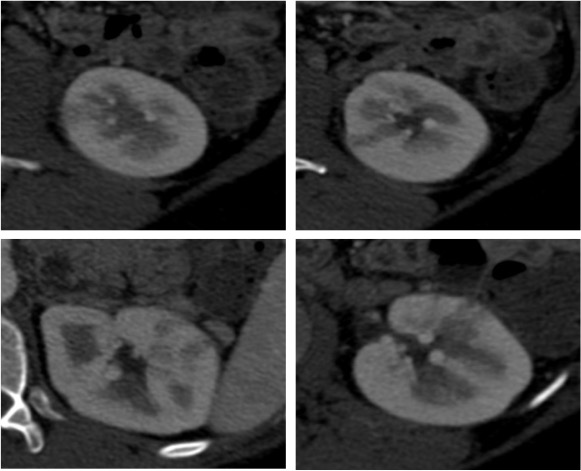

Se procede a realizar TC abdomino-pélvico con contraste en fase nefrográfica y excretora:

Conclusión: se nos presentó un caso de un paciente con una sospecha de infección renal complicada ya que tras cuatro días de tratamiento antibiótico no hubo mejoría. Ante los hallazgos observados en TC, podemos establecer el diagnóstico de pieloureteritis renal izquierda con signos de hidroureteronefrosis leve hasta vejiga.

La TC es la técnica de elección para diagnosticar una pielonefritis ya que permite valorar la anatomía, la fisiología y los hallazgos patólogicos intra y extrarrenales. Soulen et al. confirmaron la validez de esperar 72 horas antes de realizar una prueba de TC en pacientes con sospecha de pielonefritis. En esta serie, el 95% de los pacientes con pielonefritis NO complicada presentaron resolución de la fiebre en 48 horas y el 100% en 72h.

Es de acuerdo universal que el TC pre y post contraste es la técnica de elección para valorar pielonefritis atípicas o complicadas, superando a la ecografía gracias a su gran capacidad de detectar anomalidades parenquimatosas.

- Protocolo: TC abominopélvico sin y con contraste en fase nefrográfica (70 seg) +/- fase tardía ( a los 7 – 10 min) solo si se sospecha obstrucción.

- TC sin contraste permite valorar la presencia de gas, cálculos, hemorragias, aumento del tamaño del riñón, masas inflamatorias y obstrucciones.

- TC con contraste: Las áreas afectadas del parénquima aparecen como zonas con baja atenuación debido al edema. Las áreas hiperdensas son menos frecuentes y corresponden a focos de hemorragia. Estos hallazgos son mejor valorables a través de la aplicación de contraste, ya que un TC en vacío pueden pasar desaprecibidas.